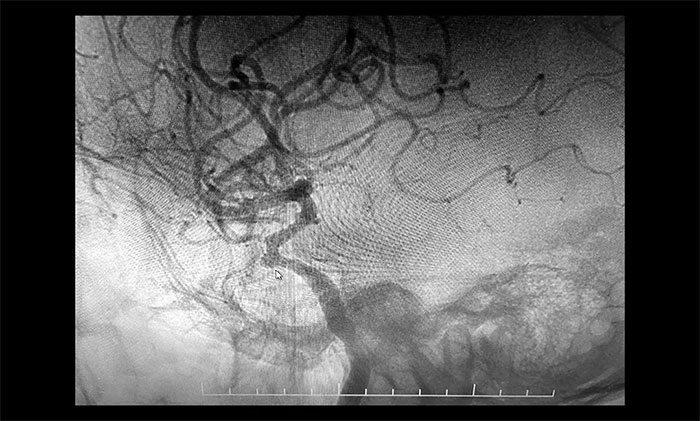

于耀宇主任為患者完善檢查,CTA提示右側(cè)頸內(nèi)動(dòng)脈C4段可疑小丘樣隆起,不排除動(dòng)脈瘤。為進(jìn)一步明確診斷,于耀宇主任在導(dǎo)管室局麻下為患者行DSA腦血管造影以明確診斷,結(jié)果顯示:右側(cè)頸內(nèi)動(dòng)脈C4段可見(jiàn)3mmx3.5mm寬頸動(dòng)脈瘤,海綿竇段可見(jiàn)輕度狹窄。

▲ 右側(cè)頸內(nèi)動(dòng)脈C4段見(jiàn)動(dòng)脈瘤